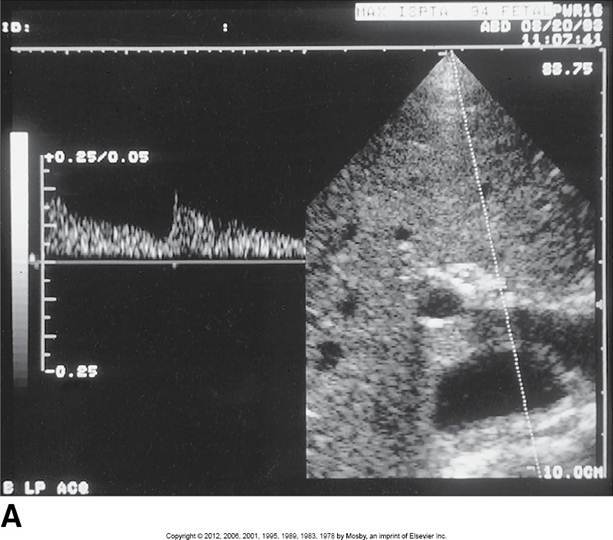

Proximal aorta

High systolic peak

Low diastolic comp.

Clean window